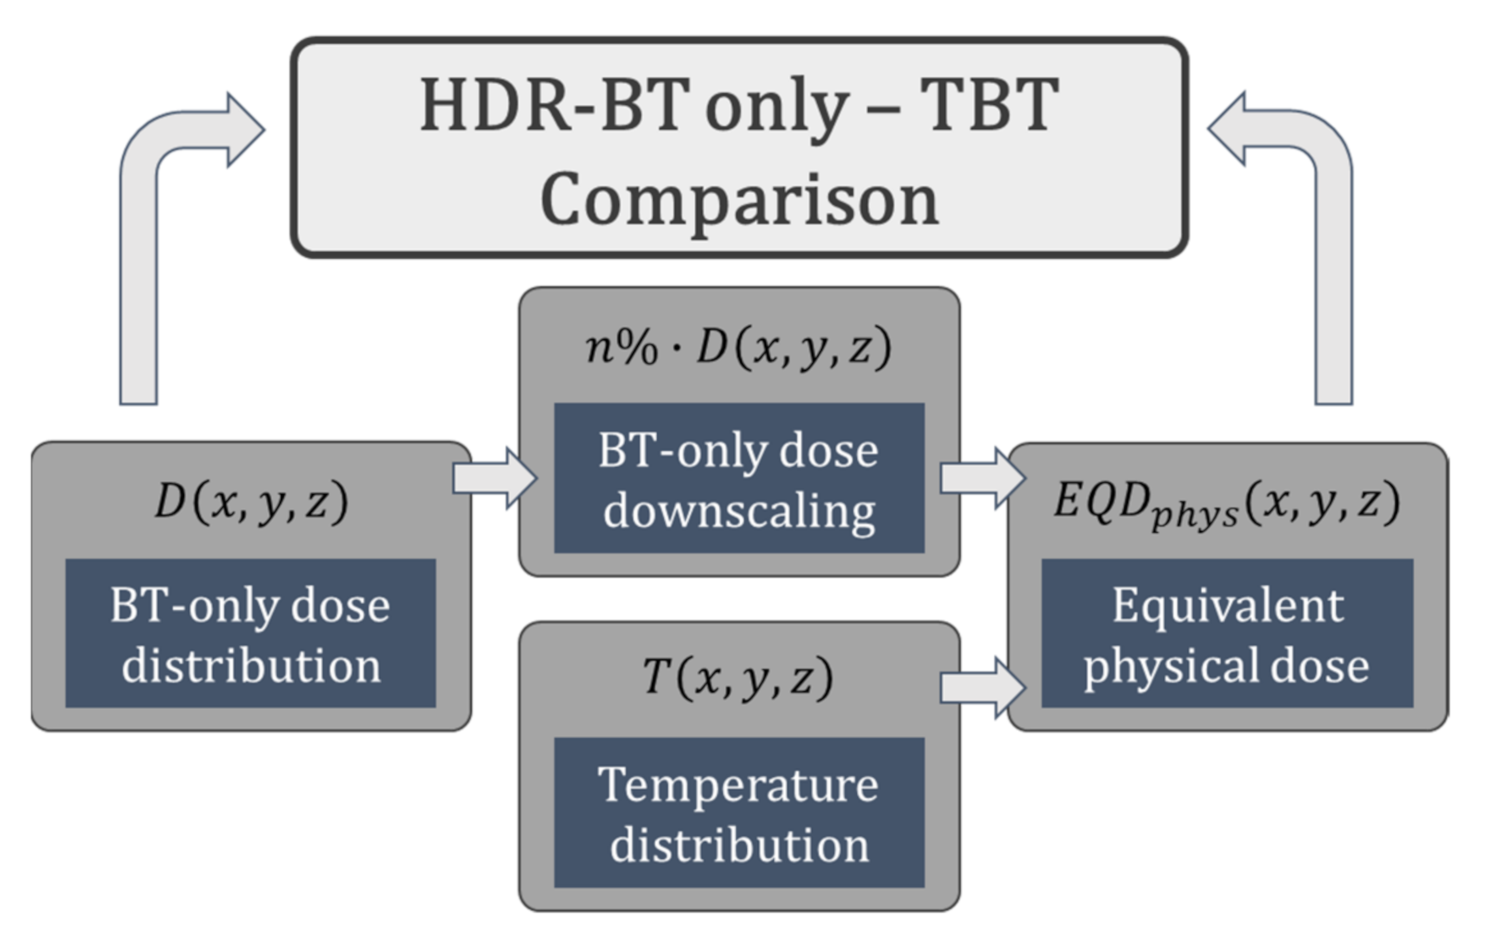

2.6. Thermoradiobiological Modeling

2.7. Thermoradiobiological Objective Function and Optimization Algorithm